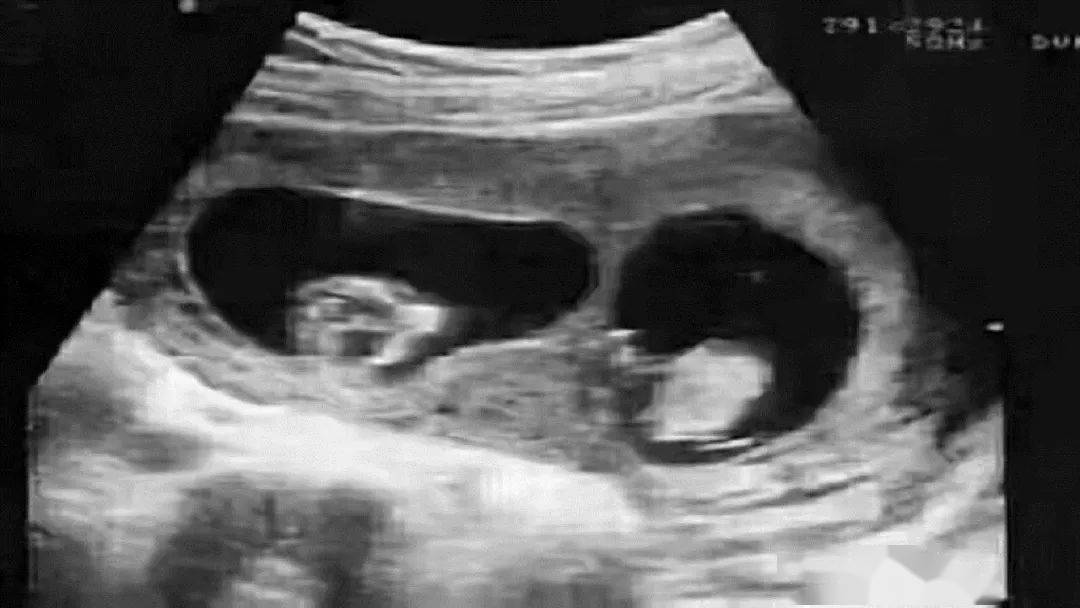

2014年,外國一對夫婦通過試管嬰兒生了一個寶寶,本來是件歡喜高興的事兒,可是幸福太短暫,後來夫妻倆竟發現孩子的血型竟然夫妻倆的血型對不上。兩人懷疑是醫院的疏漏,或許是做試管時出了意外。

最終,還是專家解開了謎團,專家解釋說:這可能就遇到了鑒定行業中非常罕見的嵌合體案例,也就是說,這位「爸爸」身體內攜帶有兩個人的DNA,可能他在媽媽肚子裡的時候,還有一個雙胞胎弟弟,但是這個雙胞胎弟弟的胚胎沒有發育下來,反而和他的胚胎出現了融合,導致這個「爸爸」攜帶兩個人的DNA出生,而且他把弟弟的DNA傳給了孩子。